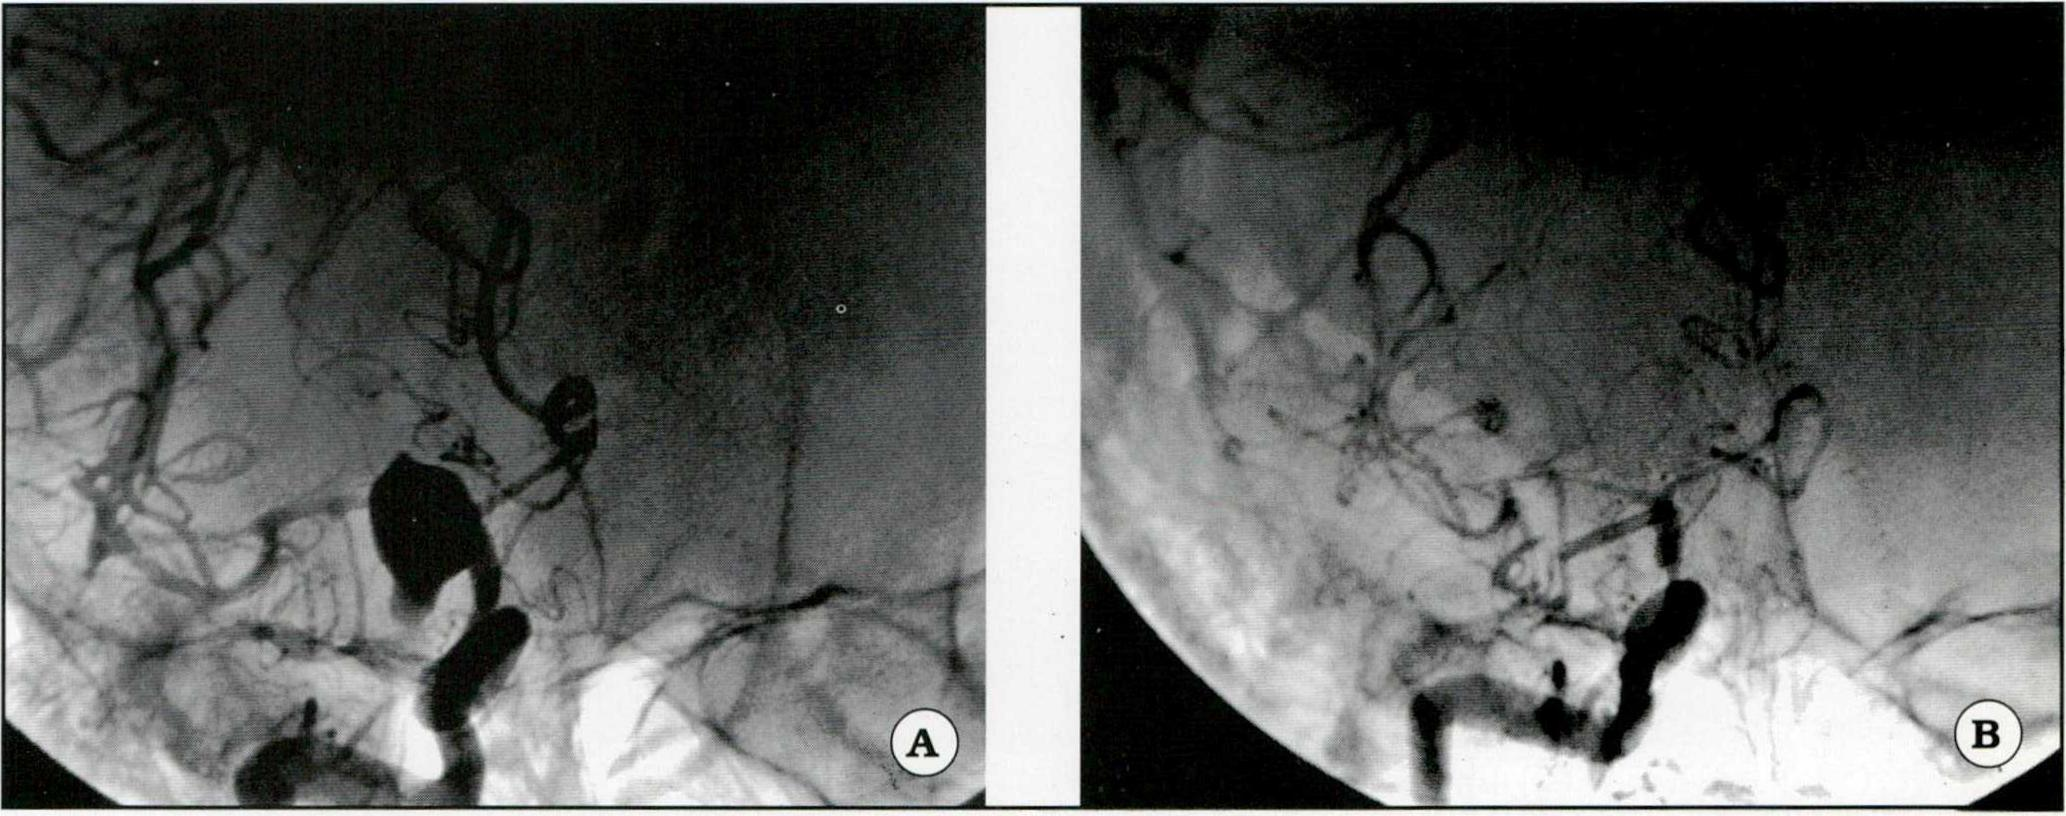

Fig 2. A. Angiografía en posición frontal de un aneurisma carotídeo. B. Se visualiza el clipado del aneurisma con importante vasoespamoo.

Fig. 3. A. Aneurismas múltiples. Se observa el aneurisma silviano derecho y un clip aplicado a un aneurisma carotídeo izquierdo. B. Clipado del aneurisma silviano.